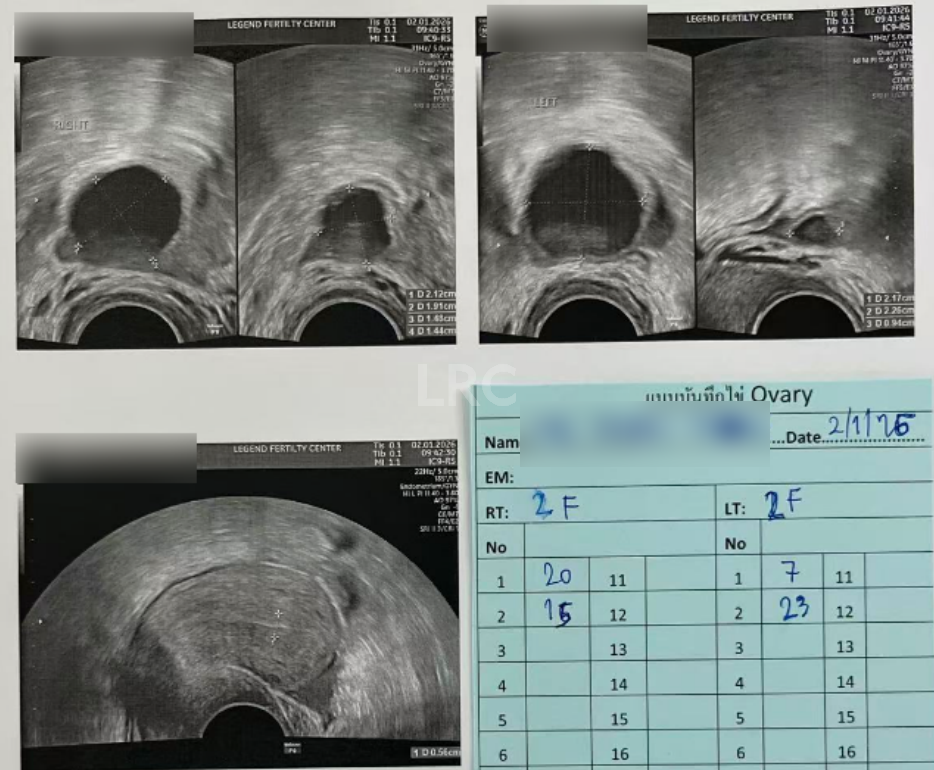

促排第十天

阴超检查:

- 右侧卵泡 2 颗 (20,15mm)

- 左侧卵泡 2 颗 (23,7mm)